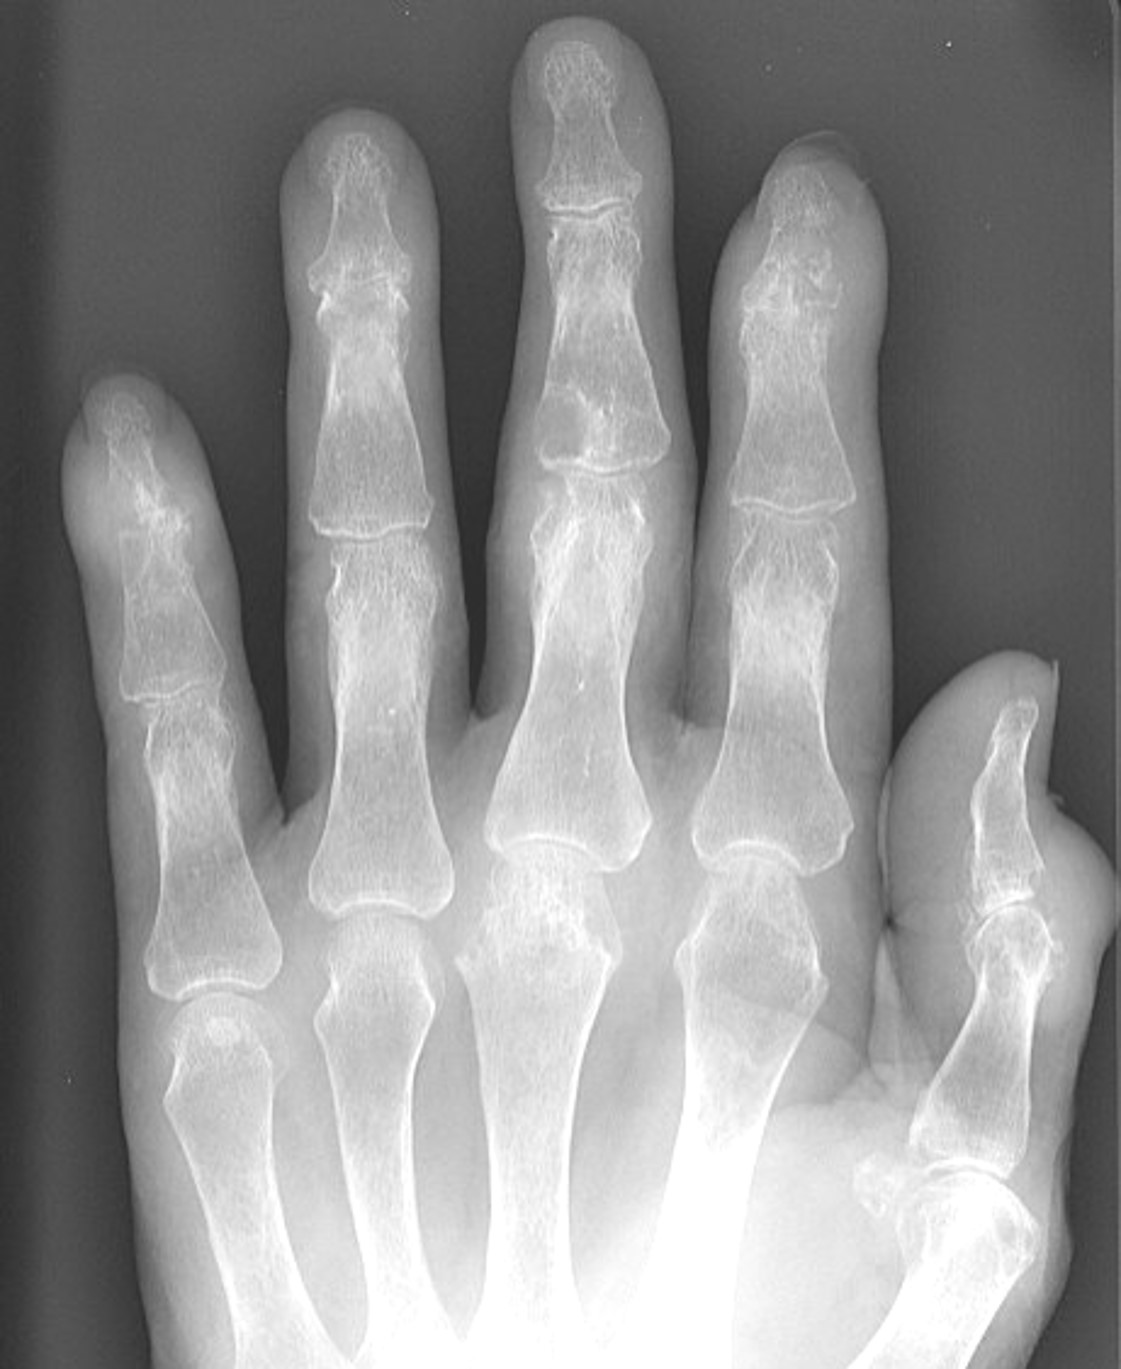

単純XP:図2(図2)

図 2.左手指単純 XP

所見︓左第 3 中節骨に関節の辺縁から少し離れたところに “overhanging edge” とよばれる痛風結節による浸食像をみとめる